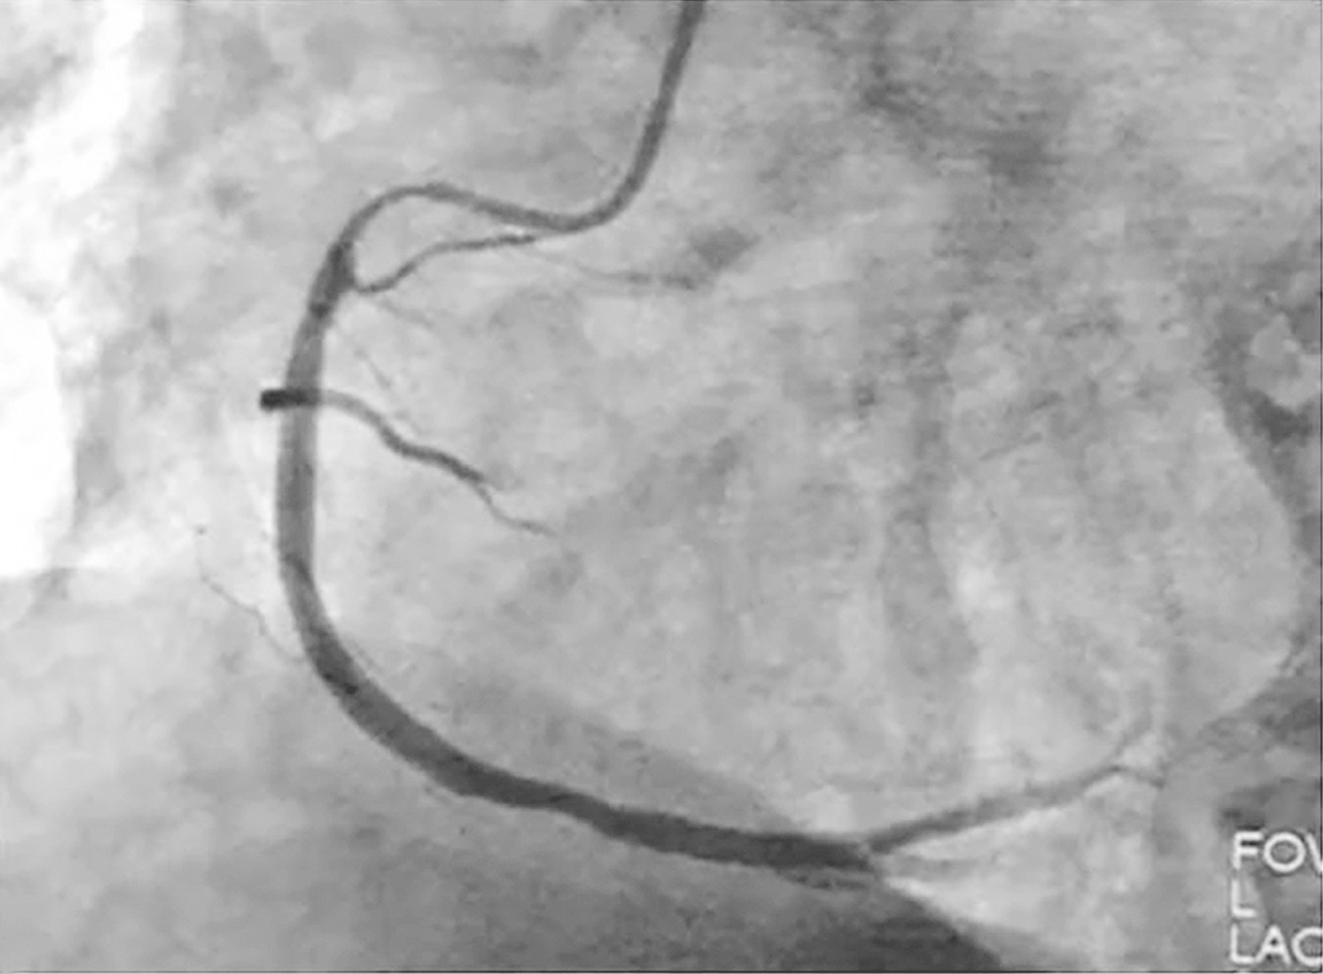

危急!82岁女性突发一过性意识丧失伴胸闷2小时 如何…

1小时条评论82岁女性,突发一过性意识丧失伴胸闷2小时。无神经系统定位体征,不支持急性脑血管病,伴有胸闷、憋气,心率、呼吸增快,血压、血氧饱和度下降,P2亢进,心肌损伤标志物正常。如何诊治? 【病例介绍】 患者女性...